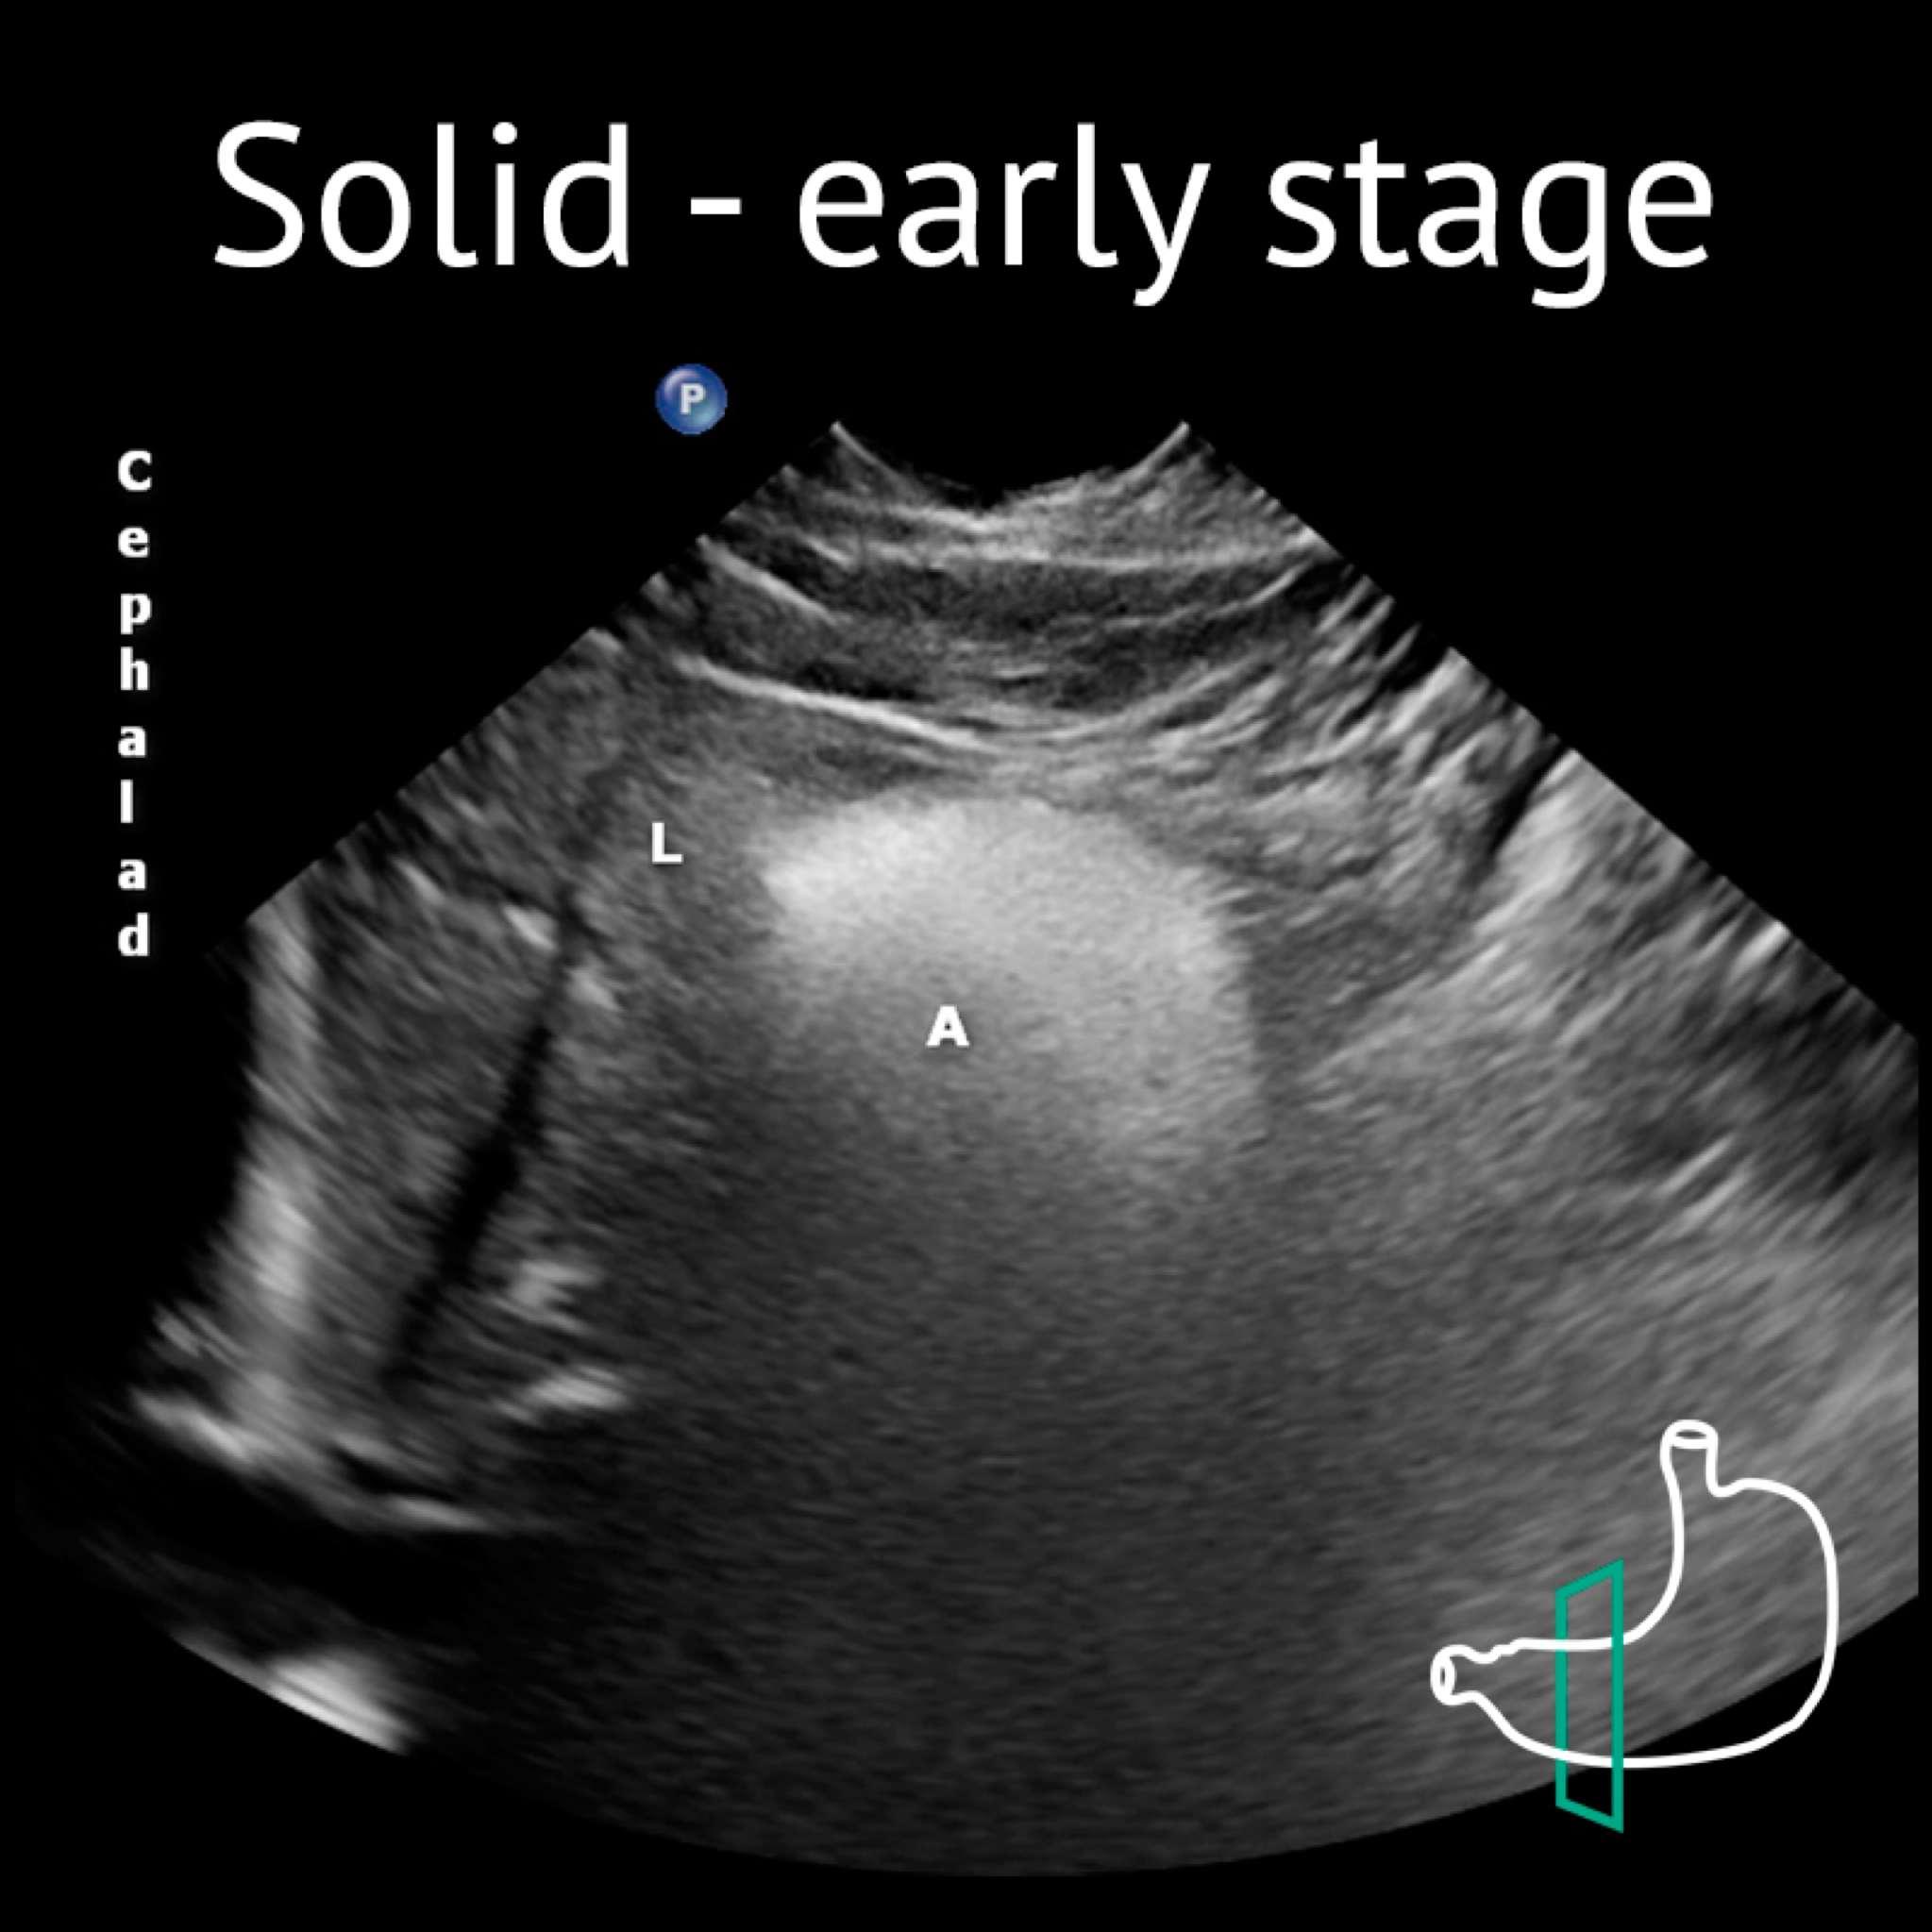

A: antrum; Ao: aorta; L: liver; P: pancreas; Sma: superior mesenteric artery